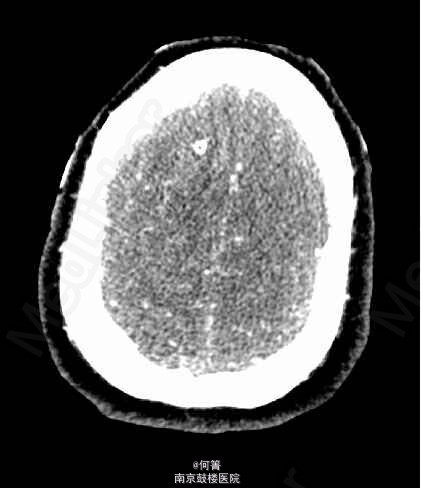

患者,女,59岁,因“突发头痛伴意识障碍4天”入院。入院前4天,患者无明显诱因突发头痛,伴有恶心、呕吐,呕吐多次胃内容物,继之出现意识障碍,呼之不应,小便失禁,无四肢抽搐,送至当地院就诊,行头颅CT示颅内出血,予侧脑室外引流穿刺及输液治疗,患者意识逐渐恢复,转至我院进一步治疗。既往高血压病史4年。

查体:BP:158/103mmHg,余生命体征平稳。专科查体:嗜睡状,呼之能应,查体欠合作;右侧额部留置有脑室外引流管,引出淡红色脑脊液;颈项强直。 辅助检查:CTA:蛛网膜下腔出血,脑室积血,右侧额叶血肿伴灶周水肿,脑实质明显肿胀,中线局部左移,右侧脑室见引流管。基底动脉瘤,其内密度不均匀,可疑血栓形成,大小约1.0x1.5cm;左侧椎动脉颅内段动脉瘤,大小约0.6x0.5cm;左侧大脑中动脉M1及M2D段交界区动脉瘤,截面大小约0.6*0.6厘米;右侧颈内动脉终段、左侧大脑中动脉M1段及椎动脉管腔不均匀,局部增粗,管壁欠光整。